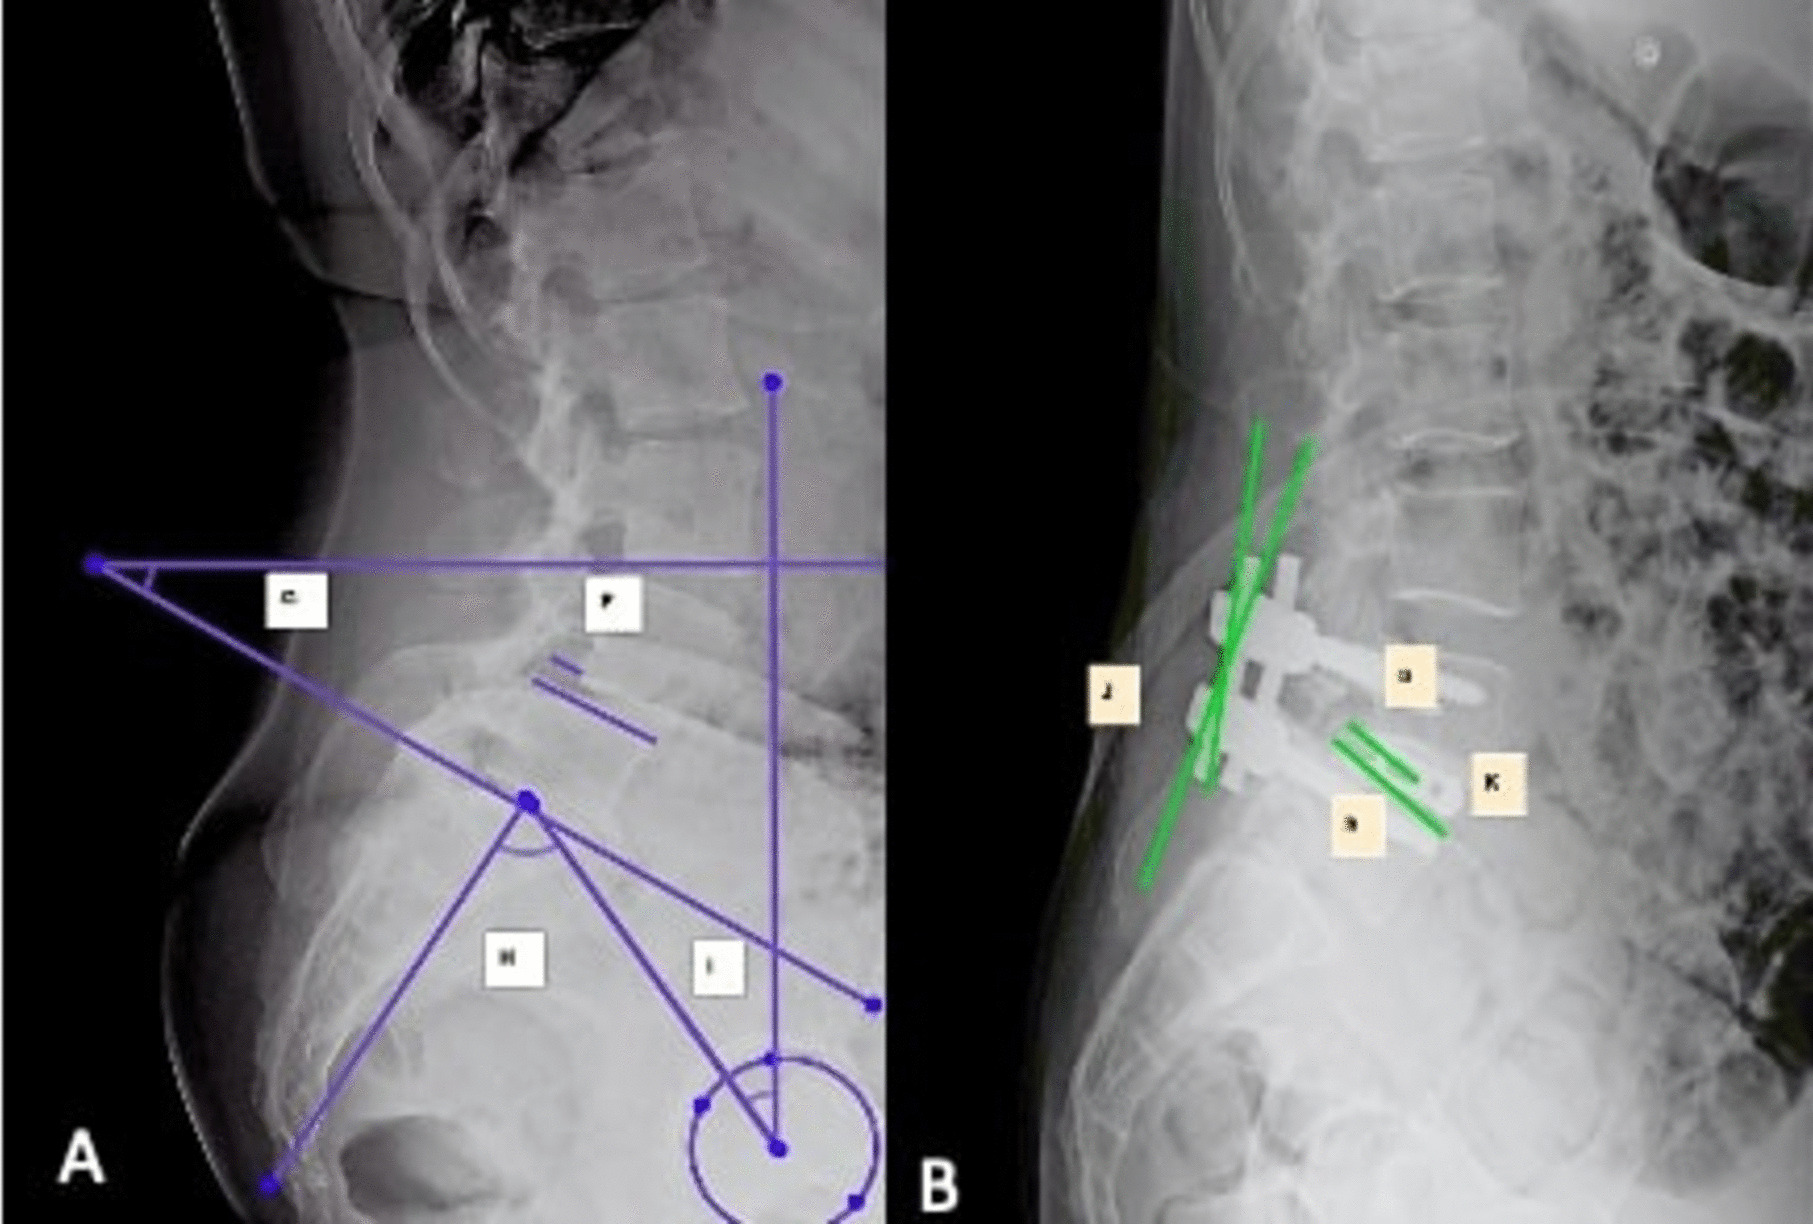

Methods: A single-centre, retrospective study on 74 patients with degenerative and lytic lumbar spondylolisthesis who underwent single level transforaminal lumbar interbody fusion (TLIF) surgery between August 2020 and July 2022 with a minimum follow up of 1 year. Radiographic measures included disc angle(DA), SLL, lumbar lordosis(LL), anterior/posterior disc height(ADH/PDH), spondylolisthesis percentage(SP) and pelvic parameters like pelvic incidence(PI), pelvic tilt(PT) and sacral slope(SS). Surgery-related measures included cage position, spondylolisthesis reduction rate, rod contouring and disc height restoration rate(DHRR). For analysis, change in SLL ≥ 8° indicated increased segmental lumbar lordosis(ISLL), and < 8° indicated unincreased segmental lumbar lordosis(UISLL).